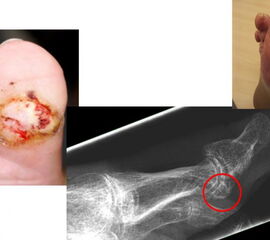

Chronische Ulcera führen längerfristig zu einer oberflächlichen Infektion des Fußes. Über die Zeit kann sich die Infektion in tiefere Gewebsschichten ausbreiten und den Knochen befallen. Bei einem ungünstigen Verlauf kann der Fuß so stark geschädigt werden, dass eine Amputation nicht mehr zu vermeiden ist. Neben einer schlechten Durchblutung und einer verminderten Gefühlswahrnehmung des Fußes (Polyneuropathie) führen häufig mechanische Druckstellen durch Knochenkanten zu Hautschäden. Um frühzeitig die Entstehung von Hautläsionen zu vermeiden, können wird häufig empfohlen störende Knochenkanten durch kleine operative Eingriffe abzutragen, bevor es zu einer Druckstelle kommt.

Bei Hallerzehenfehlstellung kann es zu Druckstellen bzw. Hautschäden an der Zehenspitze oder über dem Zehenmittelgelenk kommen.Sollten hier konservative Therapiemaßnahmen (Polsterung/Schuhzurichtung) versagen, ist eine operative Korrektur der Hammerzehe sinnvoll, bevor offene Stellen entstehen, die dann zu Eintrittspforten für Keime werden.

- Operative Behandlung von Druckstellen durch Knochenvorsprünge (Exostose)

Im Bereich des Fußes können an verschiedenen Stellen Knochenanbauten (Exostosen) z.B. im Rahmen von Arthrose zu Druckstellen und dann zu Hautschäden führen. Hier ist die prophylaktische Abtragung des Knochenüberstandes sinnvoll. Immer wieder verhindern auch Knochenkanten die Heilung einer schon vorhandenen Hautwunde. In vielen Fällen lassen sich heute solche Knochenkannten minimalinvasiv in der sog. „Schlüssellochtechnik“ ohne große Operation entfernen.

Zum Lesen der Bildbeschreibung und Vollansicht bitte Bild anklicken. Fotos: Alexander Mehlhorn

- Operative Behandlung von Druckstellen durch Überlänge eines oder mehrerer Mittelfußknochen

Anlagebedingt oder nach Amputationen kann es zu einer Überlänge von einem Mittelfußknochen relativ zu den anderen Mittelfußknochen kommen. Dies führt zu einer erhöhten Druckbelastung an der Fußsohle. Zunächst treten Schwielen auf, im Verlauf kommt es dann zu offenen Stellen und einem Ulkus. Sollten hier konservative Therapiemaßnahmen (Polsterung/Schuhzurichtung) versagen, ist eine operative Verkürzung oder Anhebung des entsprechenden Mittelfußknochens sinnvoll, um den Druck zu reduzieren. Auch dies ist heute meist minimalinvasiv in Schlüssellochtechnik möglich.